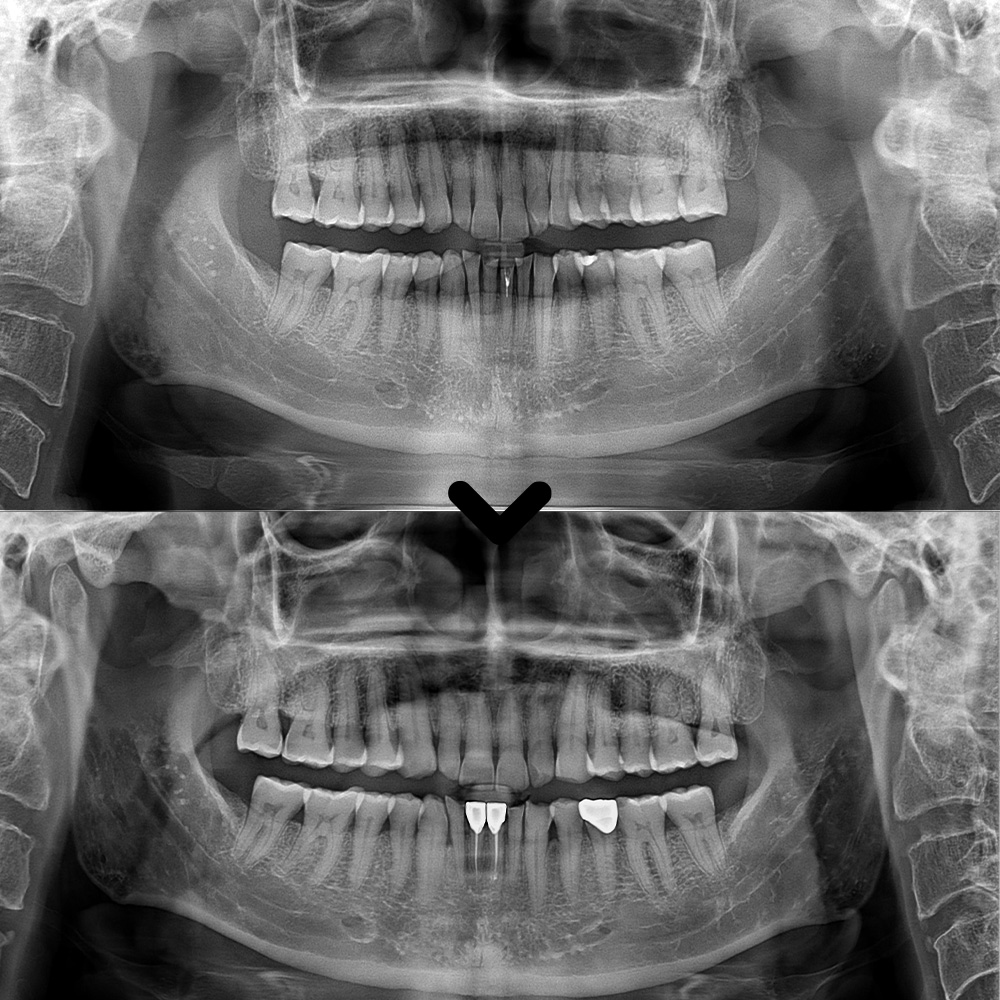

이렇게 MTA 신경치료로

앞니 자연치아를 살려

마무리하였습니다.

이후 크라운 제작을 위해

주변 치아와의 색상을 비교해본 후

원내기공소에서 크라운 제작을 진행하였습니다.

이후 크라운이 완성되어 맞춰보며

교합과 형태, 색상을

꼼꼼하게 확인하였습니다.

씹을 때 불편함은 없는지,

주변 치아와의 조화는 자연스러운지 점검한 뒤

미세한 조정을 거쳐

최종적으로 장착하였으며,

기능적·심미적으로 모두

만족할 수 있도록 마무리하였습니다.

또한 왼쪽 아래 어금니도

기존 충전재와 충치를 깨끗하게 제거 후

크라운을 제작하여 세팅해 드렸습니다.

마무리 후 사진입니다.